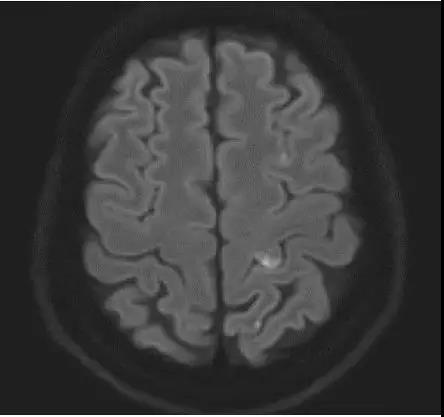

案例圖

急性腦梗死彌散加權(quán)成像